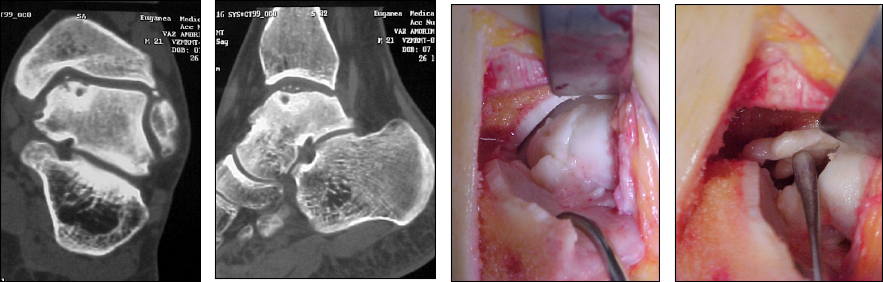

L’imaging da attuare nel sospetto di lesione condrale o sottocondrale è rappresenta da semplici Rx della caviglia in tre proiezioni ben eseguite, da una Risonanza Magnetica con macchina ad alta intensità di campo 1,5 Tesla e, talora, da una TC multislice con ricostruzione 3D allo scopo di definire meglio millimetricamente la sede della lesione e di darne le dimensioni vere, poiché la RMN in genere, complice l’edema, sovrastima la grandezza della lesione.

Come valenza diagnostica, e non solo ovviamente, ha estrema importanza l’artroscopia, indagine che in genere è contemporanea al trattamento, ma che è l’unica ad offrire un quadro reale della lesione, in termini di grandezza e gravità.

Nelle lesioni IIa e IIb di dimensioni superiori a 1 cm il trattamento è artroscopico, con asportazione del frammento instabile od affondato, cruentazione della lesione e condroplastica per stimolazione, mediante pulizia delle “spalle” della lesione e microperforazioni dell’osso sottostante.

Nelle lesioni instabili di dimensioni grandi, intorno a 1,5 cm di diametro, con frammenti mobili e vacuolizzazione cistica sottostante (Grado III e IV) il trattamento consiste nell’eliminazione del tessuto ormai necrotico e nel colmare la nicchia o con autotrapianto prelevato dal ginocchio (OATS) in misura di uno o più (tecnica detta di mosaicoplastica), oppure con tappi (plug) biomimetici, che prevedono l’inserimento di un tessuto bioattivo al posto della lesione.

La tecnica OATS prevede abbattimento e reinserzione del malleolo tibiale, specie quando la lesione è postero-mediale.

Anche la tecnica con plug biometici prevede un accesso artrotomico poiché, dovendo questi plug essere inseriti a tappo ed essendo di lunghezza intorno ad 1,5 cm, richiedono grande spazio di manovra.

Recentemente ha trovato spazio il trattamento con cellule mesenchimali (cellule che hanno un alto potenziale condrogenico ed osteogenico) prelevate dal tessuto osseo spugnoso (esempio dall’ala iliaca). Dopo l’innesto le cellule vengono ricoperte da una membrana di acido jaluronico, creando così una microcamera in cui si può riformare una cartlagine jalina e dunque meccanicamente valida. Questa tecnica ha il vantaggio di richiedere un solo intervento e può essere eseguita in artroscopia.